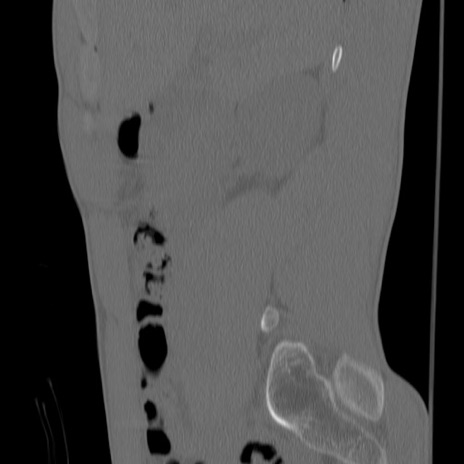

症例3 腰椎CT(矢状断像)

【症例】30歳代男性

【主訴】腰痛

【現病歴】本日旅行先で観光中に、友人と衝突し転倒し受傷。

【身体所見】麻痺なし、右下腿内側前面外側、左下腿内側に知覚鈍麻・しびれ

異常所見と診断は?

腰椎CT